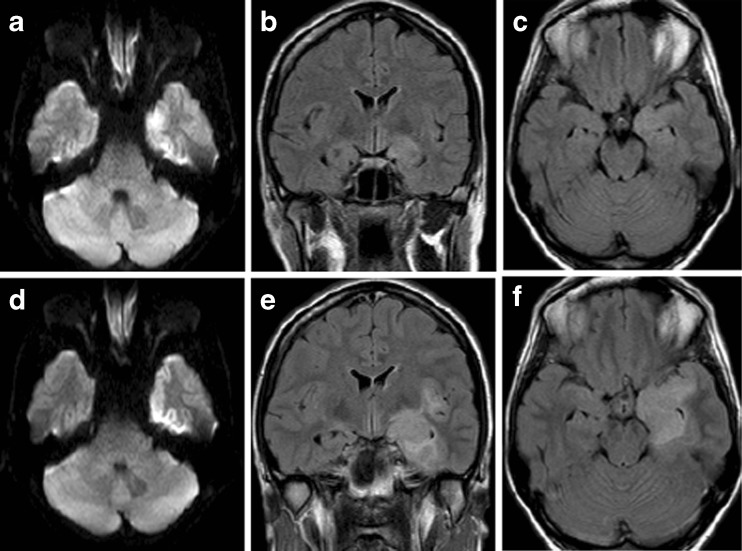

Case 1: A 33-Year-old Woman with Complications of HSVE

A 33-year-old woman presented with a generalized tonic-clonic seizure after several days of upper respiratory tract infection, headache, fever, confusion, and word-finding difficulty. Brain MRI revealed diffusion restriction and FLAIR hyperintensity with edema in the mesial temporal lobe and hypothalamus (Fig. 2). EEG demonstrated periodic discharges in the left temporal area. Lumbar puncture revealed 7 nucleated cells/μl (90 % neutrophils), 295 erythrocytes/μl, and normal glucose and protein. HSV-1 PCR was positive in the CSF and she was treated with aciclovir. One week into her hospitalization, after initially improving she developed right lateral rectus palsy and depressed level of consciousness. Repeat MRI demonstrated increased edema in the left temporal lobe. The patient eventually recovered but she was left with subtle language deficits. Follow-up MRI 6 months after her HSVE demonstrated cystic encephalomalacia in the left anterior temporal lobe.

Fig. 2.

Magnetic resonance imaging in acute herpes simplex virus-1 encephalitis. (A) Diffusion restriction on diffusion-weighted imaging (DWI) in the left mesial temporal lobe that corresponded to (B, C) fluid-attenuated inversion recovery (FLAIR) hyperintensity. (D) On day 8, with clinical deterioration, there was increased fluid restriction on DWI in the left mesial temporal lobe with tracking along the cortical ribbon that corresponded with (E, F) increased FLAIR hyperintensity and swelling